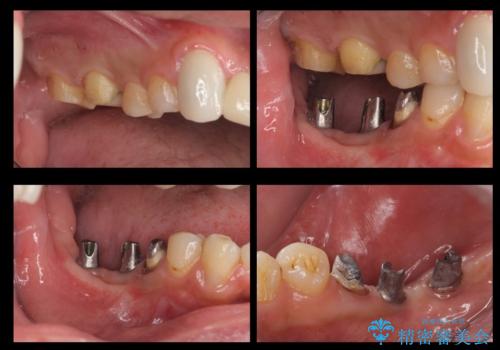

また、歯並びの矯正をするのではなければ、右上の八重歯は、犬歯を抜くか、奥に入っている歯を抜くかになるとお伝えしました。結果、根の長い犬歯を残して右上の前歯を抜歯しブリッジにしました。また、前歯の神経は極力取らないで治療を行いました。(結果神経を取る治療は前歯には行っておりません)

右下奥歯二本はインプラントにしました。(横浜桜木町歯科院長 大元先生による)

前歯の治療を先に行い、見た目を改善した後、奥歯の治療を行いました。